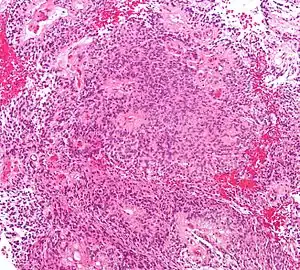

| Micrograph of an ependymoma. H&E stain. | |

Ependymomas are composed of cells with regular, round to oval nuclei. There is a variably dense fibrillary background. Tumor cells may form gland-like round or elongated structures that resemble the embryologic ependymal canal, with long, delicate processes extending into the lumen; more frequently present are perivascular pseudorosettes in which tumor cells are arranged around vessels with an intervening zone consisting of thin ependymal processes directed toward the wall of the vessel.[2]